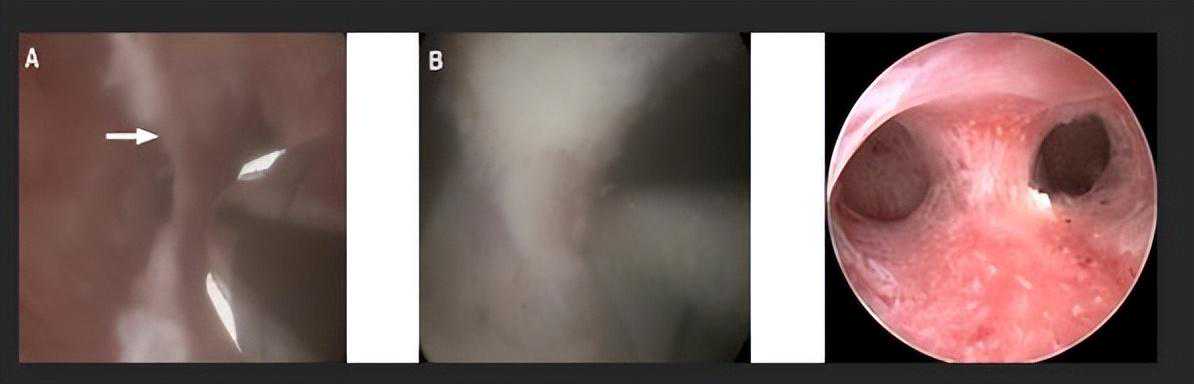

纵隔子宫属于先天性子宫发育畸形,通常对性生活无直接影响。但若伴有阴道纵隔,同房时可能会产生疼痛感。在辅助生殖术前检查中,若发现纵隔导致了反复流产或不孕,则需进行宫腔镜手术。若妇科阴道镜显示阴道同样存在发育畸形,可配合进行阴道整形手术,以改善生活质量及后续受孕条件。